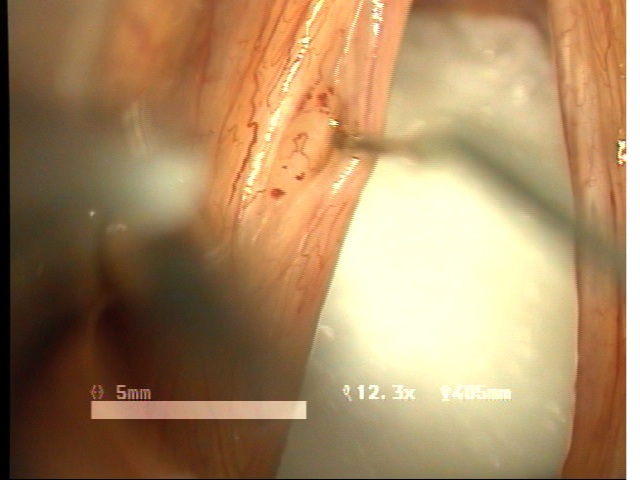

예송이비인후과 음성센터 김형태원장은 현재까지 난치성질환으로 특별한 치료방법이 없었던 "성대구증을 동반한 성대점막교(mucosal bridge of vocal fold)" 의 새로운 수술적 치료방법으로 "Sandwith mucosal flap surgery" 수술방법을 최초로 개발하여 시행한 치료결과를 얻어 예비보고로서 제82차 대한이비인후과학회 학술대외에 발표하였습니다. 이번에 발표한 새로운 수술방법은, 특별한 치료방법이 없었던 성대질환에 새로운 수술적치료방법을 제시한 것으로서 매우 높은 음성개선효과를 나타내는 것을 확인할 수 있었습니다.

제82차 대한이비인후과학회 학술대회는 2008년 4월 25일(금)-27일(토) 까지 서울 그랜드힐튼 호텔에서 열렸습니다. 이번에 발표한 연구논문은 기존의 난치성질환으로 특별히 치료방법이 없었던 "성대구증을 동반한 성대점막교"에 새로운 치료의 길을 제시한 것으로 목소리 개선에 뛰어난 장점과 효과를 입증할 수 있었습니다. 국내에서 최초로 난치성 음성질환자들의 치료에 사용된 수술방법의 수술후 치료결과에 대한 임상연구결과와 내용은 아래와 같습니다. ![]() ![]() ![]() ![]() -------------------------------------------------------------------------- * 동영상 ... more 제목 : New surgical technique for mucosal bridge of vocal fold : sandwich mucosal flap surgery 목적 : 성대 점막교( mucosal bridge)는 파열된 성대낭종이나 성대구증등에 의해 생긴 점막의 관통된 연결을 갖는 성대질환으로 수술적 치료 후 음성개선이 매우 어려운 성대질환이다. 성대 점막교는 단순절제시 음성개선이 어려운 질환으로서 특별한 수술적 치료방법이 없는 상태이다. 이에 음성보존을 위한 치료방법으로 sandwich mucosal flap을 이용한 새로운 술식을 보고하며, 이 술식의 치료결과와 음성학적 변화를 알아보고자 하였다. 방법 : 2005년 4월부터 2007년 4월까지 예송이비인후과에서 성대점막교로 진단되어 sandwich mucosal flap 술식으로 수술을 시행받은 6명의 환자를 대상으로 후향적인 분석을 시행하였다. 원인적인 요인과 동반질환으로는 파열된 표피양낭종 3례, 성대구증 2례, 폴립양성대1례였다. 조사대상은 남녀 각각 3례 였으며, 평균연령은 34.8세였다. 평균추적기간은 12.4개월이었다. 6례 모두 sandwich mucosal flap surgery를 시행하였으며 1례에서 PDL 성대수술을 추가로 시행하였다. 술후 2개월과 6개월에 음성분석검사와 후두스트로보스코피검사를 통해 객관적인 음성평가를 시행하였으며, 음성개선에 대한 주관적인 음성만족도를 측정하였다. 통계적 유의성은 Wilcoxon Signed Ranks Test로 검정하였다. 결과 : 음성개선에 대한 주관적인평가로서 수술전 Voice Handicap Index는 평균 20.9에 비해 16.4로 호전되었으며, 공기역학적검사상 성문하압은 감소되었으나 MPT은 오히려 감소되었다. 음성분석검사상 sPPQ, sAPQ, NHR, DSH는 모두 통계학적으로로 의미있게 감소하였다. 후두스트로보스코피검사상 6례 모두에서 성대점막파동의 의미있는 호전을 확인할 수 있었다. 합병증으로서 모든례에서 초기 애성이 두드러지게 나타났으며, 점막피판의 탈락이나 점막봉합사로 인한 이상은 초래되지 않았으며, 기침, 이물감 또는 객담과 같은 증상은 나타나지 않았다. 결론 : 성대점막교의 새로운 수술방법으로서 음성개선을 위해 시도된 sandwich mucosal flap surgery 가 매우 만족스러운 음성학적 치료결과를 나타내고 매우 유용한 술식이라 생각된다. |